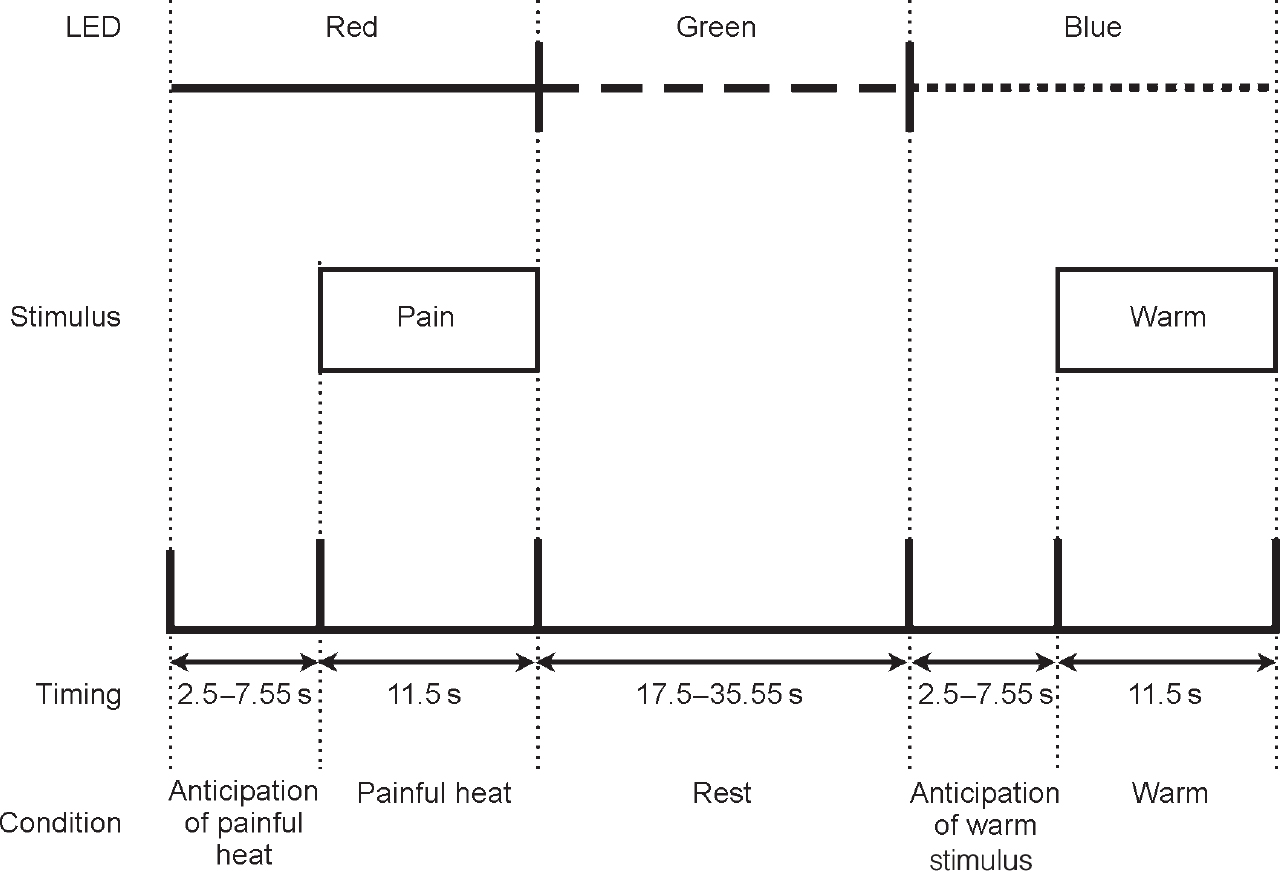

A Peltier thermode was used to apply thermal stimuli to the dorsum of the left hand, as described previously (Reference Ploghaus, Tracey and GaitiPloghaus et al, 1999). Stimulus intensities were chosen with the subject in the scanner, and for each subject individually; two stimuli that were consistently described by the subjects as ‘painfully hot’ and ‘clearly warm, but not hot’ were chosen. Three coloured light-emitting diodes (LEDs) (red, green, blue) were mounted at the subjects' feet and could be viewed through a mirror in the magnet bore. During the experiment, subjects received seven noxious and seven comfortable warm stimulations in pseudorandom order. Each type of stimulation was signalled consistently by a certain colour LED for each subject, randomised across subjects (Fig. 1). The coloured LED signals preceded the onset of thermal stimulation by a pseudo-randomly varied interval with a mean of 7.5 s (s.d.=5 s) and stayed on during thermal stimulation, which was applied for 11 s. Between conditioning trials subjects had a rest period that also was pseudo-randomly varied (mean duration=26.5 s, s.d.=9 s) and signalled by the third coloured LED. Subjects were instructed to work out the contingency between LED colour and thermal stimulation.

Fig. 1 Diagrammatic representation of study method (light-emitting diode (LED) colours were randomised across subjects).